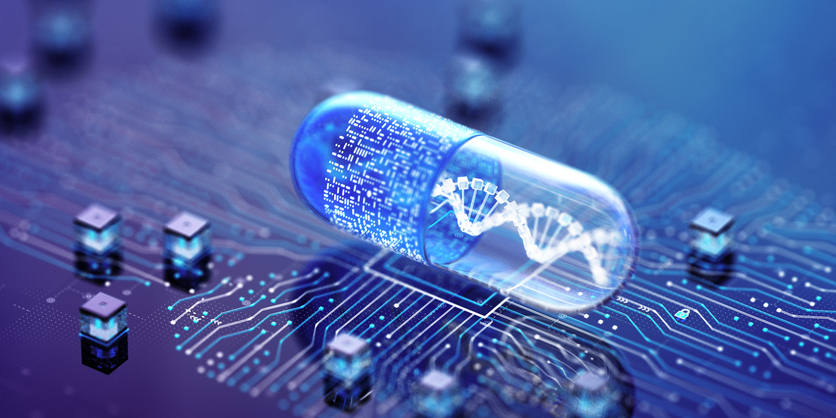

Posted inBiotechnology

Handheld Photoacoustic Probe Merges Ultrasound, Fiber Scanner

In recent years, the convergence of optical and ultrasonic technologies has revolutionized biomedical imaging, offering unprecedented insights into physiological and…